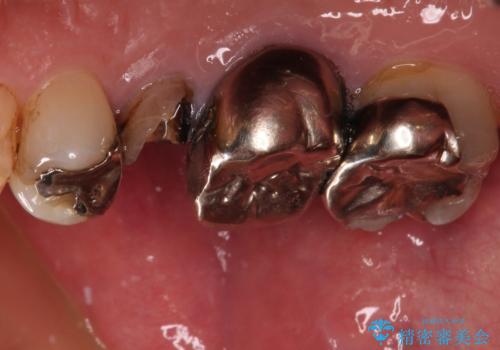

もげてしまった奥歯 オールセラミッククラウンでの補綴治療

- 食事中に歯がもげてしまったとのことで来院された患者様です。

レントゲン写真から、特に大きなむし歯などは認められませんでしたが、根管治療があまり十分に行われているとは言えない状態でした。

まずは仮歯を装着し、根管治療を行った上で土台を植立し、オールセラミッククラウンにて補綴治療を行うこととしました。

反対咬合で奥歯に負担のかかる咬み合わせのため、就寝時に強い力がかからないよう、マウスピースを装着していただくよう指示をしました。